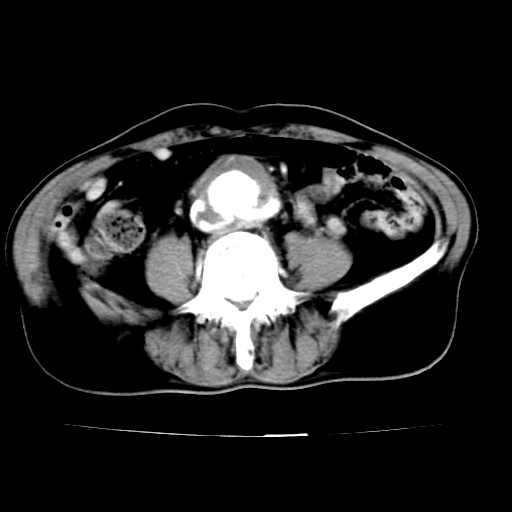

各位老师注意到下腔静脉的充盈缺损了吗?注意到动静脉漏了吗?

腹总动脉瘤伴附壁血栓形成累及髂总动脉,看起来好像有动静脉瘘,但我认为是扫描时象造成的假象。

当时是扫描的标准动脉期,可是下腔静脉与腹主动脉同步强化且幅度一致。所以我想动静脉瘘是存在的。